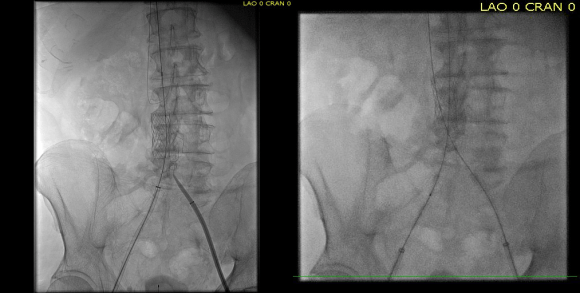

Once this is done, the iliac veins are dilated to 14mm from the IVC to the common femoral arteries. large 18mm Wall stents are deployed in a kissing fashion from the caval stent into both iliac systems and dilated to 18mm.

intervention fig 6.png

Predilatation of iliac venous systems with ever larger balloons, deployement of bilateral 18mm Wall Stents

After deployment, the Wall Stents are ballooned to 18mm. These stents were extended into the common femoral artery with 14mm nitinol stents.

intervention fig 7.png

Ballooning 18 mm Wall Stents with 18mm Atlas balloons, then extending to CFA with nitinol stents of 14mm